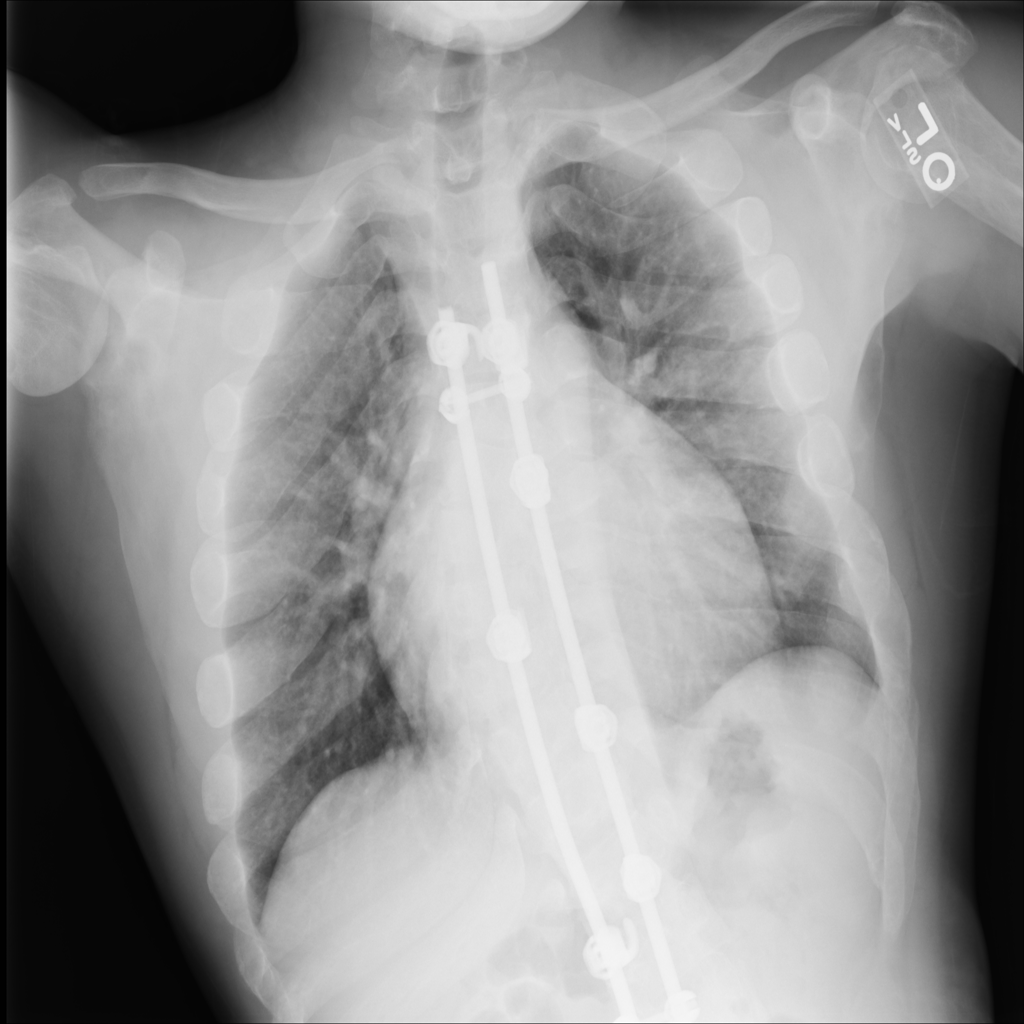

PAT-E960 · IMG-002Fibrosis

PAT-E960 · IMG-002

PA